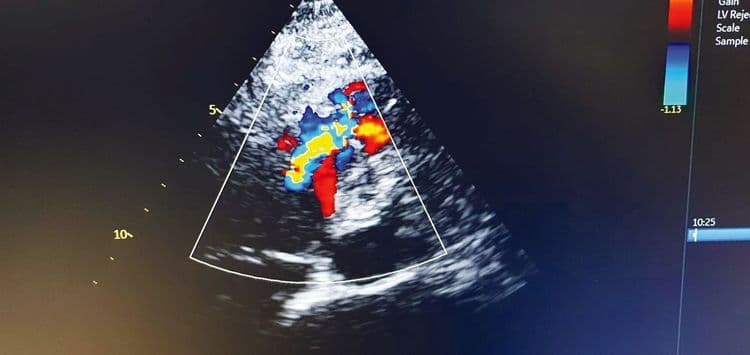

W Kociewskim Centrum Zdrowia w Starogardzie Gdańskim wykonano kolejny skomplikowany i rzadko spotykany zabieg kardiologiczny – przezskórne zamknięcie pozawałowego ubytku w przegrodzie międzykomorowej (VSD).

To wyjątkowa procedura stosowana w ciężkich powikłaniach po zawale serca. Jej powodzenie wymaga współpracy specjalistów z różnych dziedzin: kardiologii inwazyjnej, echokardiografii i intensywnej opieki medycznej.